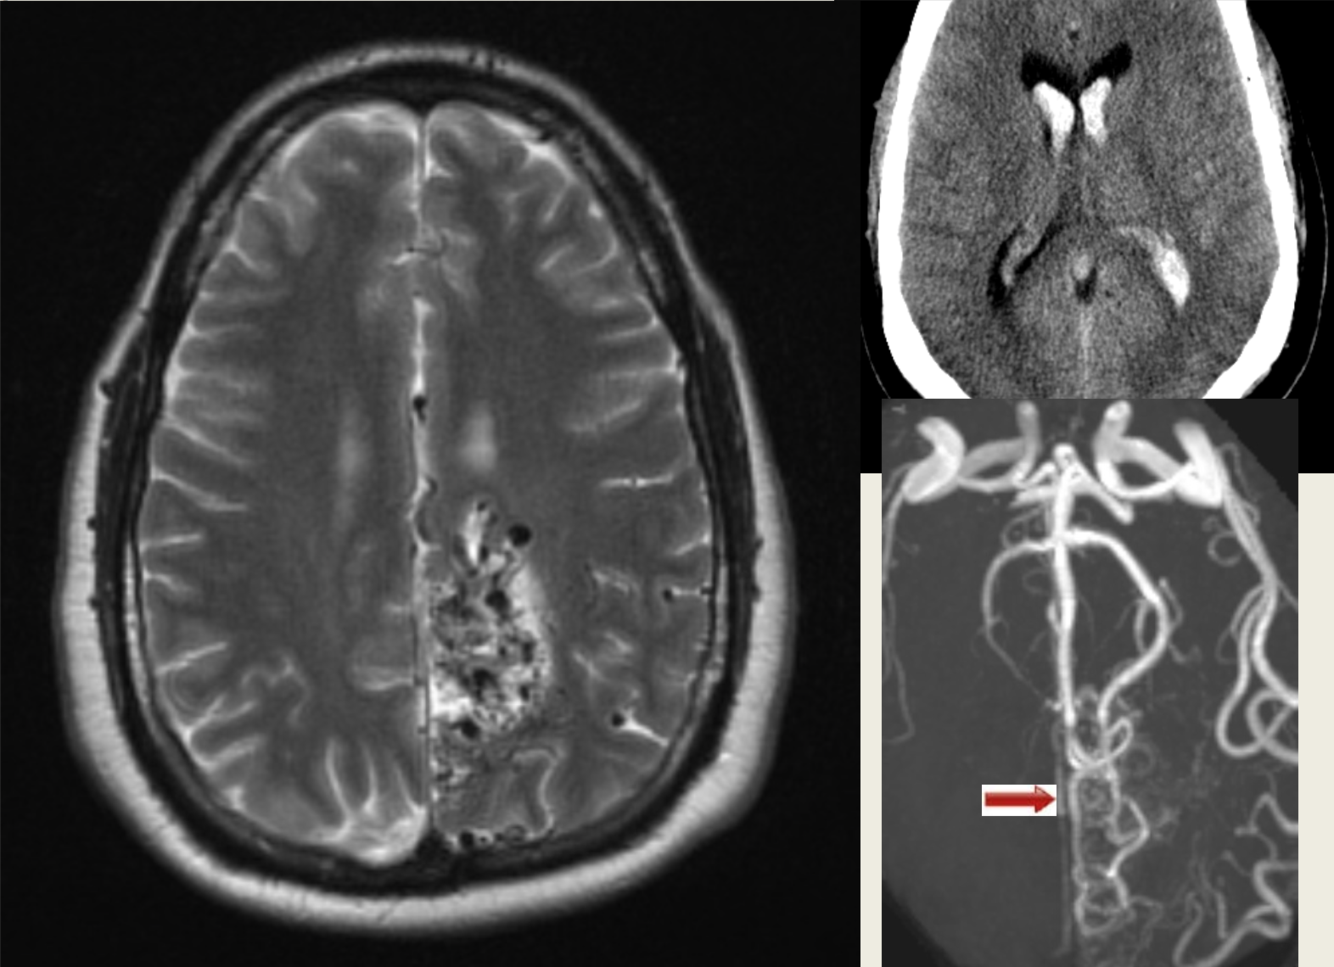

39 y/o M found down.

Intraventricular bleed due to AVM